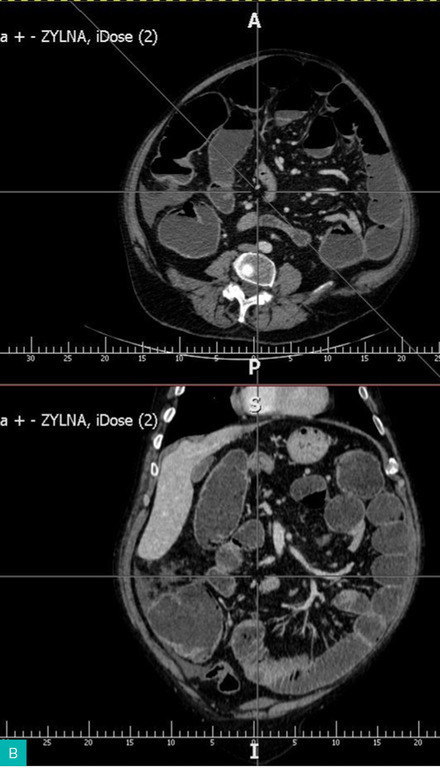

Diagnostyka: Wykonuje się przeglądowe zdjęcie RTG jamy brzusznej w celu potwierdzenia niedrożności (ryc. 1 i 2) i/lub tomografię komputerową (TK) ujawniającą rozdęte pętle jelit powyżej guza (ryc. 3).